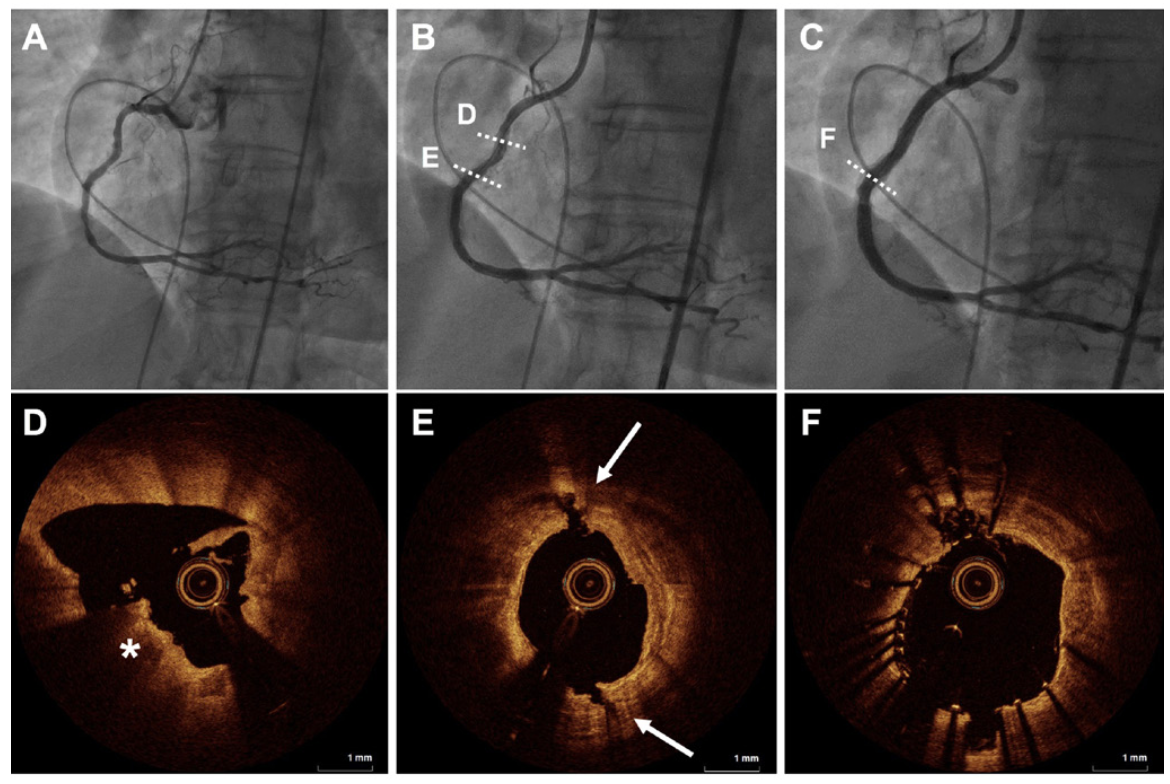

Mean reference vessel diameter was 3.67 ± 0.46 mm, with a mean lesion length of 28.9 ± 12.7 mm. Baseline diameter stenosis was 77.4 ± 11.3%. Burr sizes of 1.75 mm, 1.5 mm, and 1.25 mm were used in 52.5%, 38%, and 9.5% of patients, respectively. Average RA burr-to-artery ratio was 0.43 ± 0.05 and the IVL balloon-to-artery ratio was 0.93 ± 0.06. During the procedure, the mean number of IVL pulses delivered was 53.8 ± 20.11. A drug-eluting stent was deployed in all patients with de novo lesions and in 2 of the cases of single-stent ISR. Representative cases with angiography and intracoronary imaging are shown in Figure 1 and Figure 2.

Angiographic success and IVL balloon crossing following RA was achieved in 21 cases (100%). Procedural success was attained in 20 of 21 cases (95.2%). One death related to frank coronary perforation occurred following stent postdilation with a non-compliant balloon in a heavily calcified, severely stenosed, and tortuous right coronary artery. Intravascular imaging was not performed upfront due to severity of calcification and stenosis. Following stent deployment, postdilation was performed due to mild underexpansion in the proximal segment of the vessel that corresponded to the segment of adventitial calcium. This resulted in an Ellis 3 perforation, which required covered stent implantation and was further complicated by persistent no reflow and cardiogenic shock.